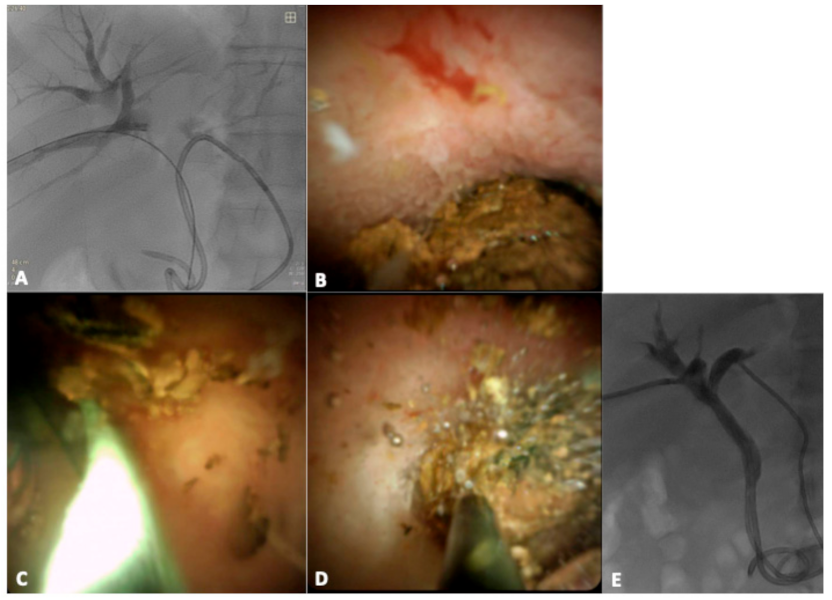

2.3. Technique and Procedure

3. Results